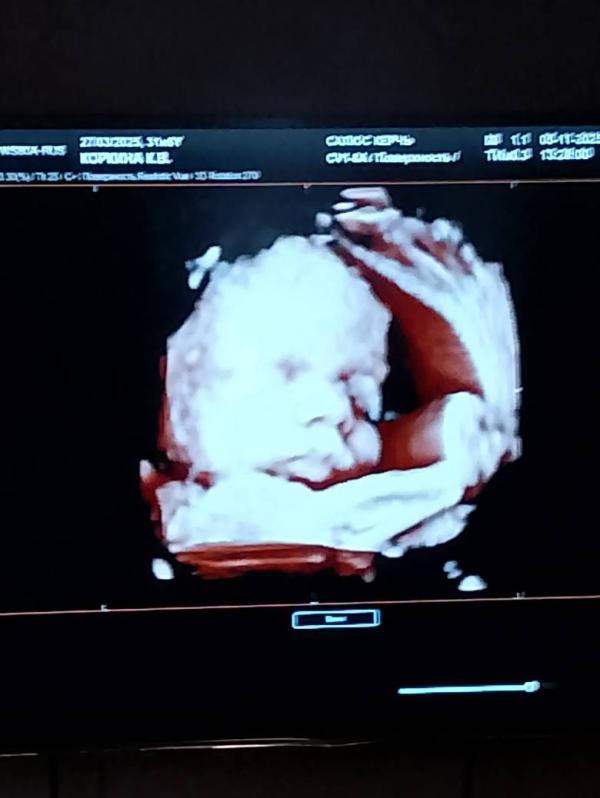

На память 🥲💕

05.11.2025

Срок 32 недели

Примерный вес 1910

Мальчишка 🥰